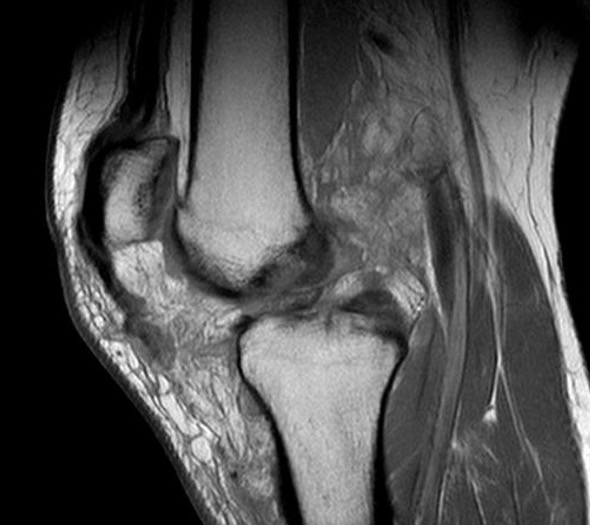

Medial dimpling Entrapped vastus medialis post knee dislocation on Coronal and Sagittal MRI